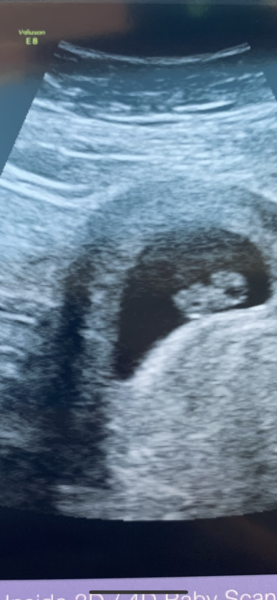

LS2020 · 17/09/2021 14:05

Scan went well today - saw the heartbeat flickering away ☺️ Said I was measuring a day behind at 6+3 but didn’t revise my EDD. Officially discharged to midwife now. Hope everyone is keeping well ❤️

@LS2020 awww look at your little bean. I am so happy to hear all was well and you saw babies heartbeat. Such lovely news ❤️❤️. That’s good that it’s helping. Hope your throat feels better soon. 🤣🤣 oh my, is your manager for real. I wish it was just a mental concept haha

LS2020 · 30/09/2021 06:31

Had my 8 week scan yesterday and little one is doing well, measuring 2 days behind but heartbeat nice and strong at 148bpm 🥰 finally getting my fitbit back hahaha

GlassLily · 02/10/2021 03:53

Congratulations @LS2020!! Gorgeous scan. Hi cute little baby 👋🏻 can't believe you are 8 weeks already!! Hope the ms isn't too bad. My nausea started at 7 weeks and it just got worse and worse until 13/14 weeks, then suddenly over 1-2 weeks it went away! So don't lose hope if it feels like it's getting worse all the time. Not to mention that ms is statistically associated with better pregnancy outcomes 🙂

@LS2020 awww look at your little baby 😍. How lovely. When is your due date? Sorry I’ve been rubbish at keeping up. We’ve all got Covid atm. Been a rough two weeks! Hope everyone is well xxx